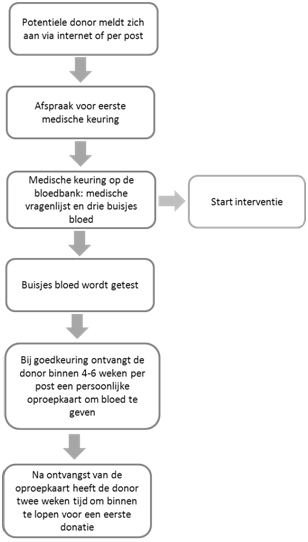

In een interventiestudie wilden we kijken of het inzetten van deze technieken leidt tot een verhoogde opkomst (Wevers, Wigboldus, Van den Hurk, Van Baaren & Veldhuizen, 2015). Daarom kregen 937 nieuwe donoren, die zich hadden aangemeld bij de bloedbank (Sanquin) na hun eerste medische keuring een extra informatieformulier. Op dit informatieformulier werd het oproepensysteem uitgelegd en eventueel aangevuld met de technieken ‘implementatie intenties’ en ‘commitment’ (zie figuur 1 ‘ start interventiestudie’). Het is binnen het oproepensysteem van Sanquin niet mogelijk om een donatieafspraak in te plannen op datum en tijd. Daarom werd aan een deel van de nieuwe donoren gevraagd of ze voor zichzelf een dag en tijdstip wilden inplannen waarop ze bloed zouden gaan doneren (implementatie-intentie). Aan een ander deel werd gevraagd of ze het informatieformulier wilden ondertekenen (commitment). Donoren kregen willekeurig één van deze technieken of een combinatie ervan. Vervolgens kreeg ongeveer de helft van de donoren een aanvullende vragenlijst over hun motivatie, waaronder vragen over intentie (“Ik blijf bloed donor totdat ik niet meer mag doneren”) en self-efficacy (“Als ik zou willen lukt het mij om bloed te blijven geven zolang mijn gezondheid dat toestaat”). Uiteindelijk werd gekeken of het uitvoeren van één van deze technieken, of een combinatie van beide, leidde tot een verhoogde opkomst na een oproep voor een eerste donatie.